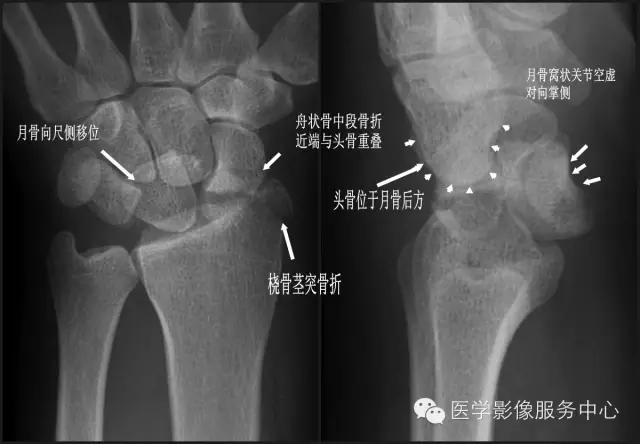

二、经茎突和舟状骨的月骨脱位 【受伤机制】 手于外撑位跌倒,腕过度背伸。 【诊断要点】

①尺骨或桡骨茎突骨折;

②舟状骨中段骨折,近端与头骨重叠;

③月骨可向尺侧移位,月骨窝状关节空虚,对向掌侧;

④头骨位于月骨后方。